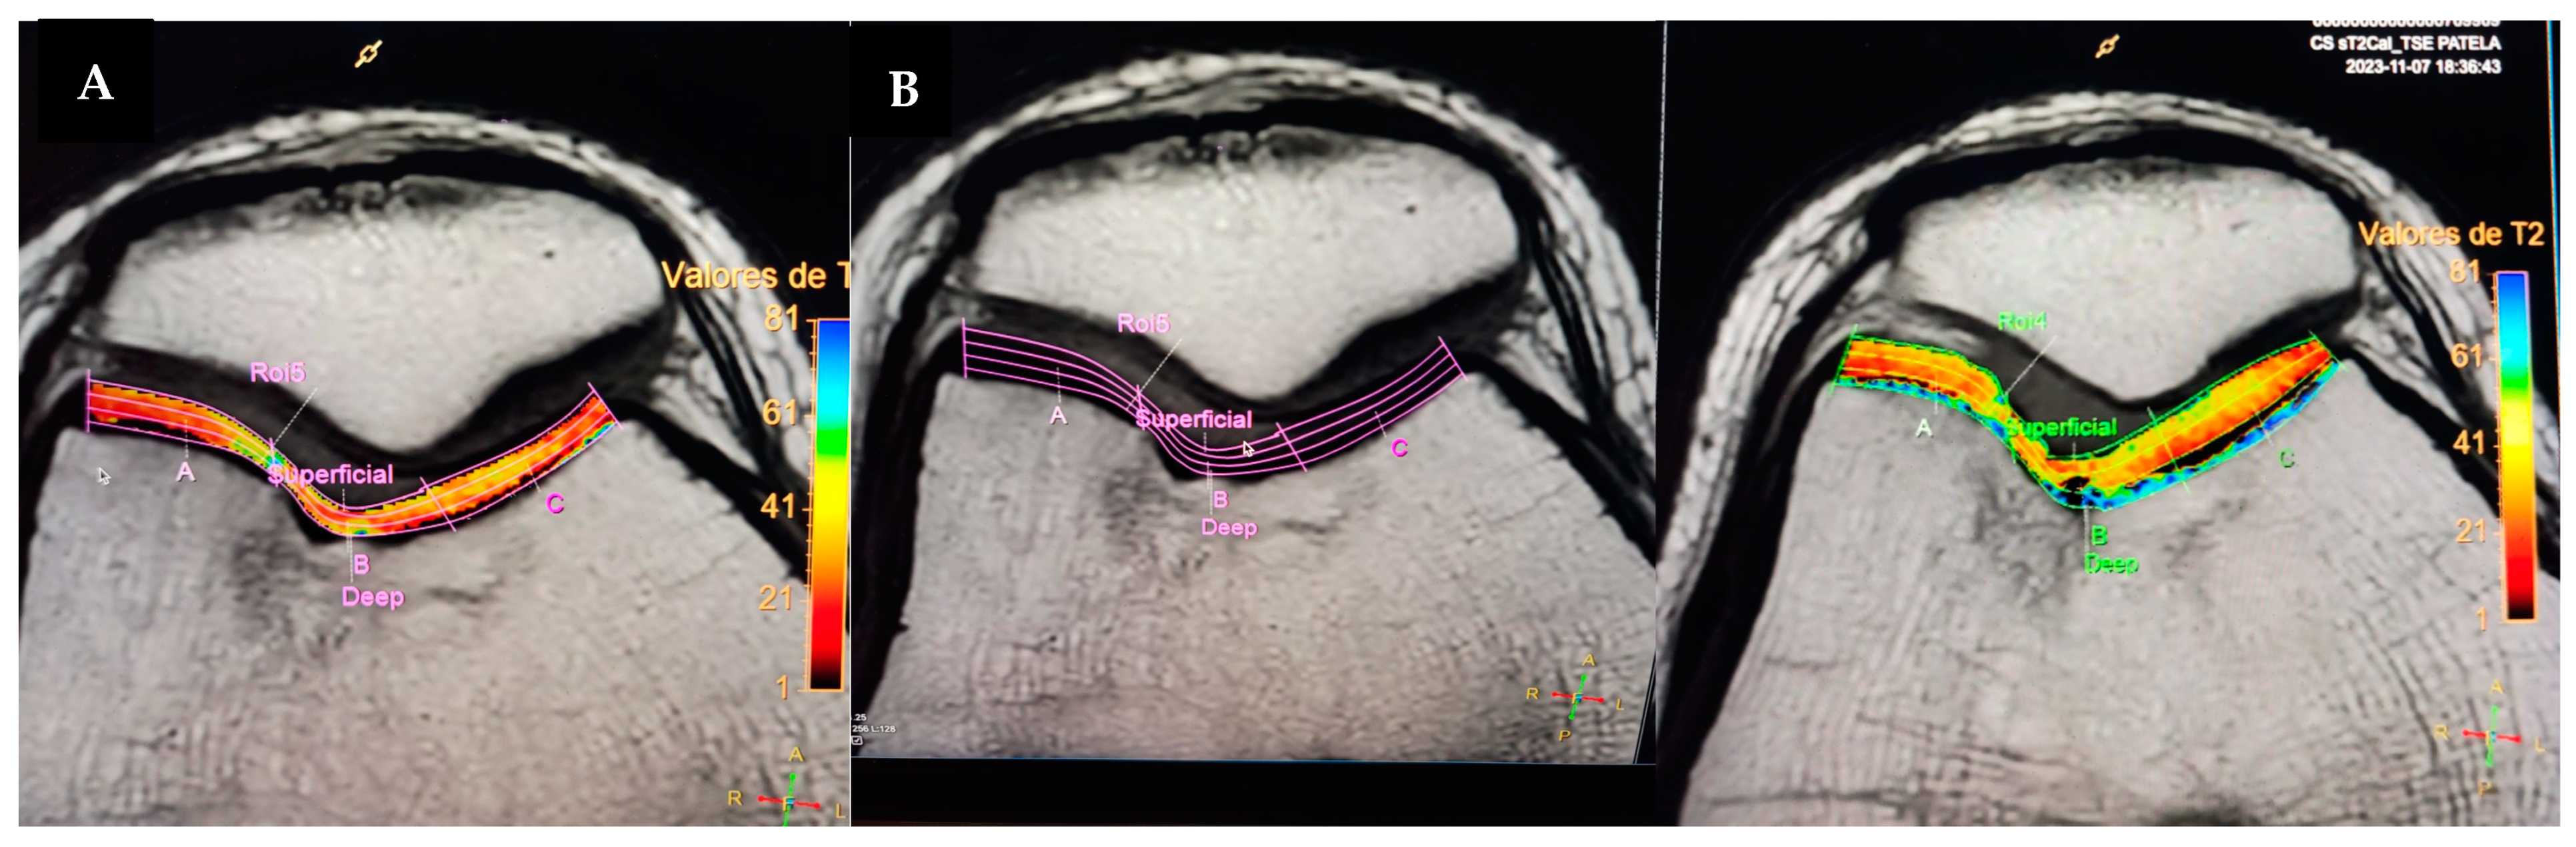

2. Case Report